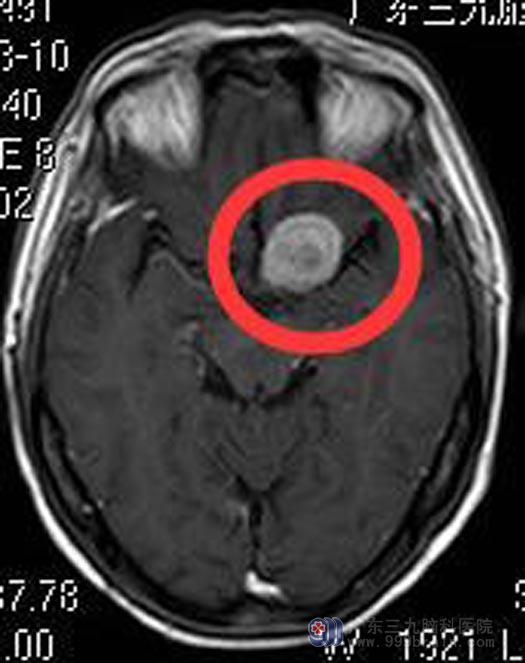

儿子赶紧带着她来到广东三九脑科医院,头颅MR检查显示:左侧鞍旁占位性病变,约2.23cm×1.90cm×2.55cm,考虑脑膜瘤可能;头颅CTA检查提示:左侧鞍旁占位性病变,其内多发斑片状钙化影及肿瘤血管,考虑脑膜瘤。